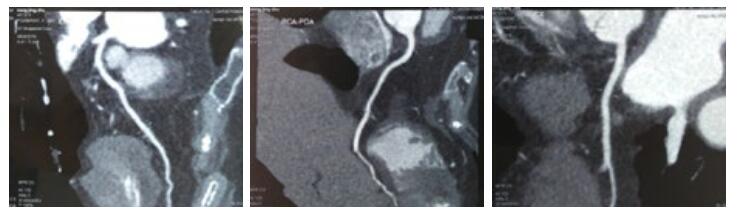

第1天,心脏超声提示:左房38 mm,左室舒张末内径50 mm,射血分数50%。左室下壁后壁运动减低,左室收缩功能减低,心律失常,二、三尖瓣轻度反流。血化验回报:血常规:白细胞(WBC)15.32×109/L,中性粒细胞(NEUT)比例55.64%,嗜酸性粒细胞(Eosinophil,EO)比例18.81%(绝对值2.88×109/L)。入院后给予左西孟旦等药物对症治疗。第3天,血常规回报:WBC 13.07×109/L,NEUT比例44.0%,EO比例42.0%(绝对值5.49×109/L)。第4天,复查血常规回报:WBC 12.6×109/L,NEUT比例43.6%,EO比例36.9%(绝对值4.6×109/L),复查cTnT 4.16 ng/mL;NT-proBNP 13 840 pg/mL。患者症状略缓解。追问病史:入院前1年曾3次就诊于外院,且反复多次出现EO异常升高,最高2.32×109/L,动态对比胸部CT情况可见游走性斑片影,且入院前1周行冠脉CTA检查未见异常。故考虑Löffler心内膜炎可能。第5天,给予甲强龙40 mg静脉,第6天复查血常规WBC 7.2×109/L,NEUT比例87.2%,EO比例0.5%(绝对值0.0×109/L)。持续给予甲强龙40 mg静脉5 d,第10天复查血常规WBC 9.5×109/L,NEUT比例70.1%,EO比例0.7%(绝对值0.1×109/L);cTnT 2.24 ng/mL;NT-proBNP 6 481 pg/mL,住院期间查ANCA阴性,曲真菌抗体阴性、C反应蛋白、降钙素原、体液免疫、风湿全项均正常。入院后11 d症状好转出院。

| 图 1 入院前1周冠脉CTA情况(A前降支;B右冠;C回旋支) |